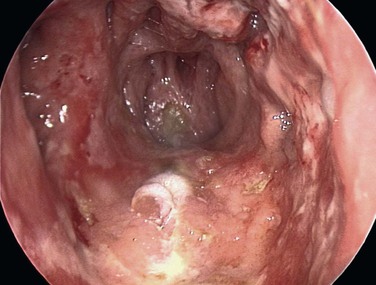

Most anterior epistaxis can be controlled with identification of the bleeding point using a headlamp and cautery. The vast majority of posterior bleeding sites can be identified by endoscopy without general anesthesia.44 The majority of posterior idiopathic bleeds are from the septum, usually from the septal branch of the sphenopalatine artery as it runs submucosally (Fig. 42-14), although some report bleeding from the lateral aspect of the middle or inferior meatus or from the posterior end of the turbinates (Fig 42-15).45 When the site of bleeding cannot clearly be identified with a headlamp, the use of a rigid nasal endoscope by an experienced endoscopist is best. The key is to identify the site of the bleeding and gain control using silver nitrate cautery or bipolar suction diathermy. Recent studies have shown that the use of endoscopic bipolar diathermy treats most epistaxis.46,47 Preparing the nose with phenylephrine or cocaine for its decongestant and anesthetic effects often helps. It is worth noting that phenylephrine has a significant decongestant effect at 6 minutes and maximum anesthetic effect after 9 minutes,48 and time must be allowed for it to take effect. An injection of local anesthetic and epinephrine gives better analgesia, if there is a sizable vessel that needs bipolar diathermy; otherwise, the patient may feel a smarting sensation.

The majority of posterior idiopathic bleeds are from the septum, usually from the septal branch of the sphenopalatine artery as it runs submucosally. The key is to identify the site of the bleeding and to gain control using bipolar suction diathermy. A severe septal deviation can make it difficult to define the bleeding point.49 Control of the bleeding avoids the discomfort associated with nasal packing and avoids admission.50 A cost-benefit analysis of 38 adult patients with epistaxis concluded that £6804 (about $10,260 U.S. dollars) could be saved by avoiding admission in 28 patients.46 Endoscopic cauterization achieves hemostasis in over 80% of patients with posterior epistaxis at the first attempt and over 90% after a second attempt.38 The bleeding point can be cauterized with the help of a nasal endoscope, which has a reported failure rate of 17% to 33%.51,52 Complications associated with this procedure are uncommon, but isolated reports describe palatal numbness from thermal damage to the greater palatine nerve, damage to the lacrimal duct, and possible damage to the optic nerve when cautery is used in a patient who has already had an ethmoidectomy.53 If by some misfortune bleeding is torrential because of trauma to the internal carotid artery in the sphenoid, prompt packing of the sphenoid sinus is required with a firm gauze pack.54 The patient is then resuscitated, and the help of an interventional radiologist is sought.